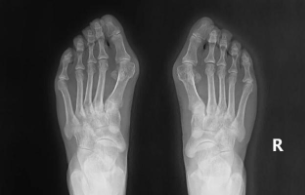

它绝不是单纯的“美观问题”:当大拇趾在第一跖趾关节处向外侧偏斜超过15度,同时第一跖骨向内侧偏移时,足部的“力学平衡”就被打破了。这个小小的畸形,会像多米诺骨牌一样,从脚掌连累到膝盖、骨盆甚至脊柱。今天,我就以骨科医生的身份,带大家彻底读懂拇外翻的来龙去脉与科学应对方法。

X光显示拇趾外翻角> 40°,或跖骨间角 > 18°,关节已经半脱位;